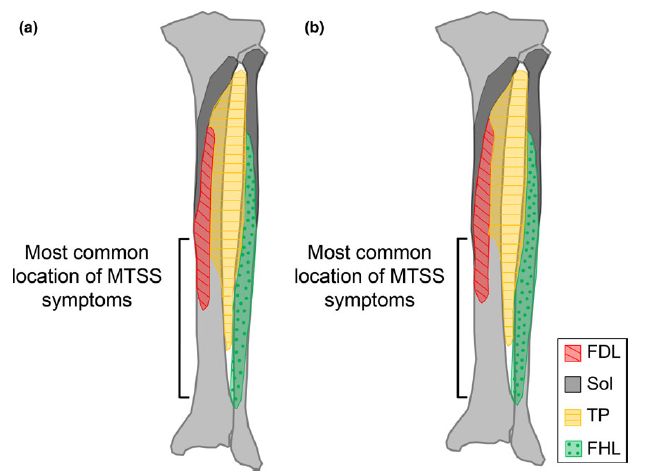

Edama M, Onishi H, Kubo M, Takabayashi T, Yokoyama E, Inai T, Watanabe H, Nashimoto S, Koga Y, Kageyama I. Gender differences of muscle and crural fascia origins in relation to the occurrence of medial tibial stress syndrome. Scandinavian Journal of Medicine & Science in Sports. 2015; DOI: 10.1111/sms.12639.